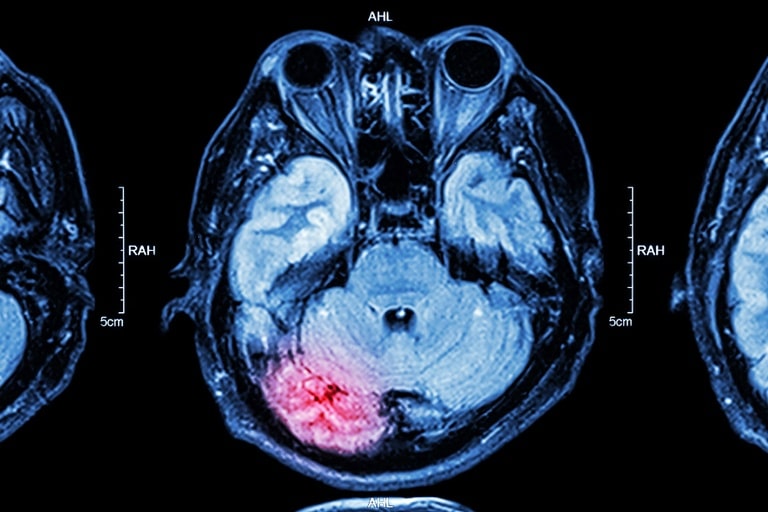

Normalmente, o AVC está associado a idosos, mas a doença tem se tornado uma preocupação também entre os mais jovens. No Brasil, cerca de 18% dos registros são de pessoas entre 18 e 45 anos.

Profissionais da saúde reforçam a importância de saber reconhecer as alterações neurológicas que podem causar os tipos de AVCs. Entre elas estão a perda de força ou sensibilidade nos membros de um lado só do corpo; alteração da comunicação, dificuldade ao falar ou para compreender; e alteração visual súbita. São menos comuns a dor de cabeça intensa; crises convulsivas; e a alteração de coordenação ou equilíbrio que não melhora.